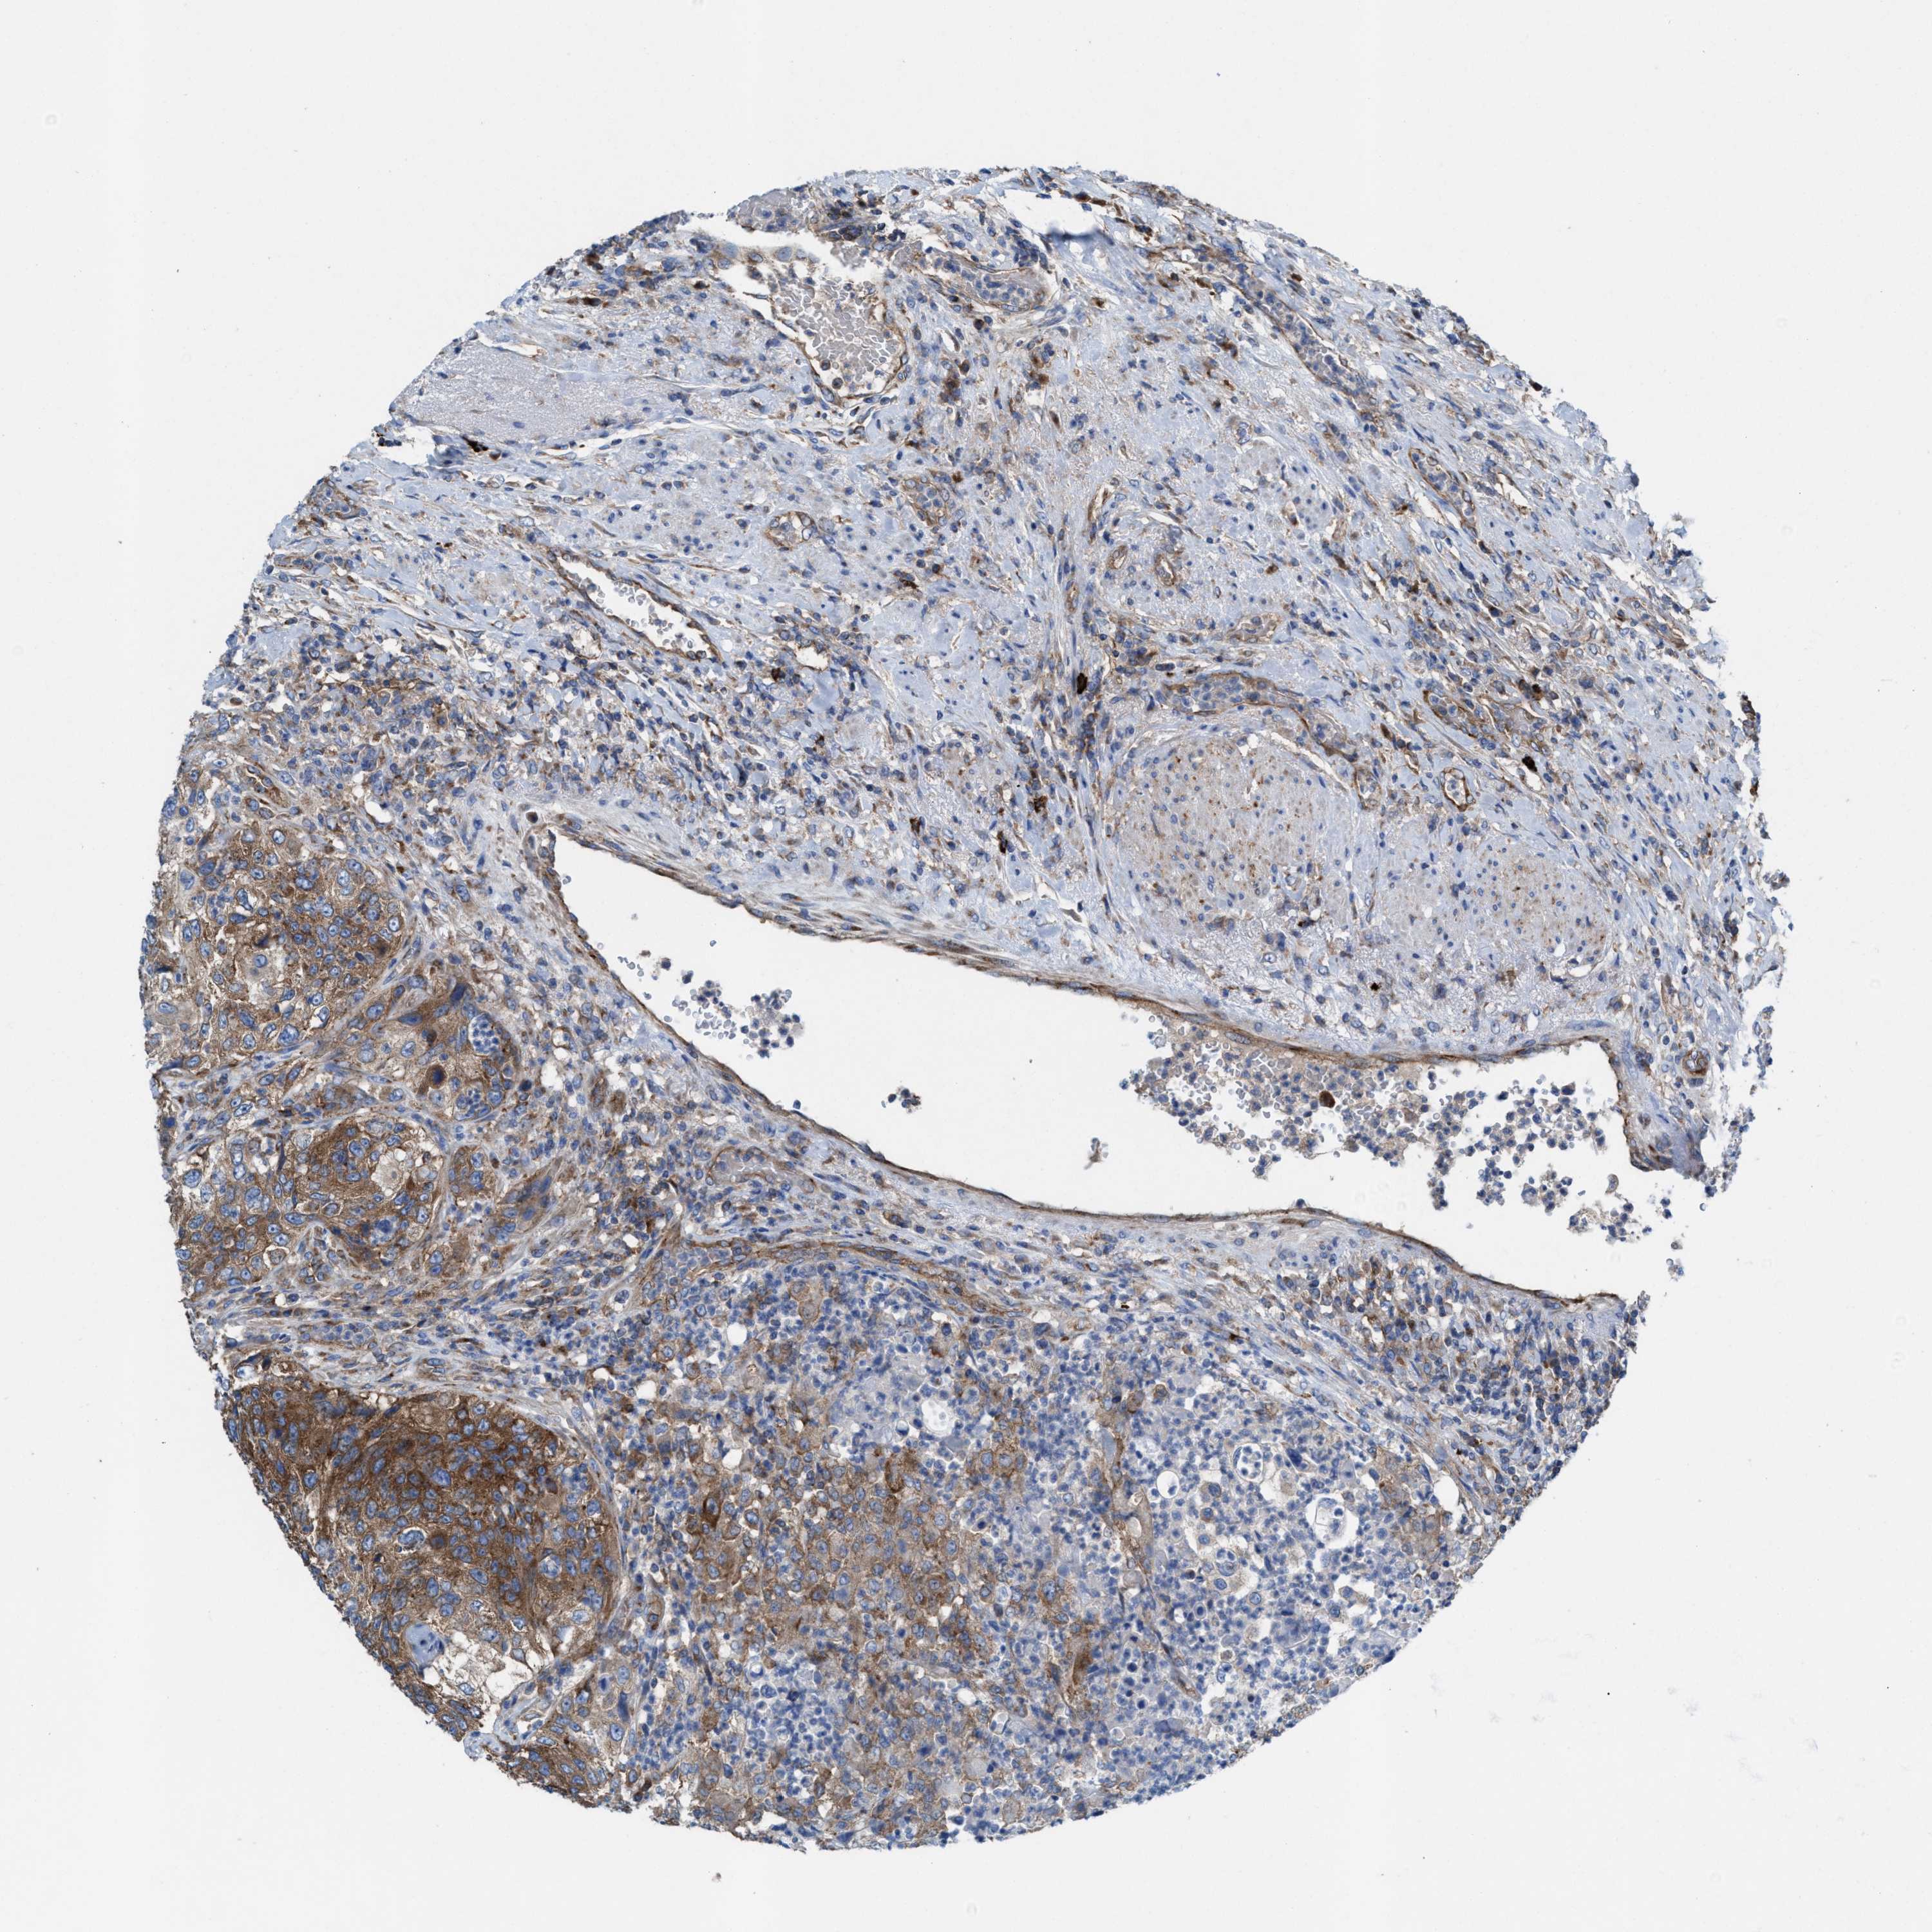

UROTHELIAL CANCER - Protein expressioni

A mouse-over function shows sample information and annotation data. Click on an image to view it in a full screen mode. Samples can be filtered based on level of antibody staining by selecting one or several of the following categories: high, medium, low and not detected. The assay and annotation is described here.

Antibody stainingi

Antibody staining in the annotated cell types in the current human tissue is reported as not detected, low, medium, or high, based on conventional immunohistochemistry profiling in selected tissues. This score is based on the combination of the staining intensity and fraction of stained cells.

Each image is clickable and will lead to virtual microscopy that enables deeper exploration of all samples and also displays staining intensity scores, fraction scores and subcellular localization as well as patient and tissue information for each sample.

Antibody HPA022251

Staining

High

Medium

Low

Not detected

Intensity

Strong

Moderate

Weak

Negative

Quantity

>75%

75%-25%

<25%

None

Location

Nuclear

Cytoplasmic/membranous

Cytoplasmic/membranous,nuclear

Urothelial carcinoma, High grade